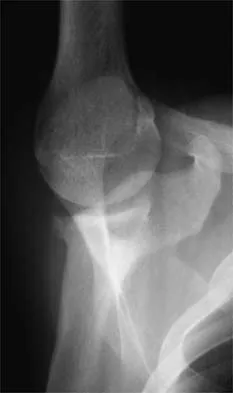

Figure 35 shows the lateral radiograph of a 15-year-old basketball player who felt a dramatic pop in his knee when landing after a lay-up. The patient reports that he cannot bear weight on the injured extremity. Management should consist of